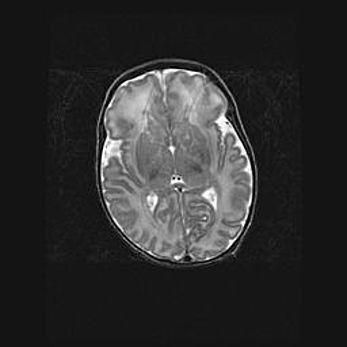

Лейкомаляция с кистозно-глиозной дегенерацией головного мозга.

Возраст: 2 месяца 25 дней

Вес: 6400 г

Окружность головы: 40 см

Срок гестации: 41 неделя

Лейкомаляцию относят к ишемически-гипоксическим повреждениям головного мозга, диагностируемым у новорожденных. При лейкомаляции в головном мозге обнаруживают очаги некроза, возникшие после тяжелой гипоксии и нарушения кровотока. В процессе морфогенеза очаги проходят три стадии: 1) развития некроза, 2) резорбции и 3) формирования глиозного рубца или кисты. Перивентрикулярная лейкомаляция (ПЛ) встречается примерно в 12% случаев среди новорожденных, обычно – у недоношенных детей, причем, частота ее зависит от массы, с которой младенец появился на свет. Наибольшее число малышей страдает лейкомаляцией, если масса при рождении 1500-2500 г.